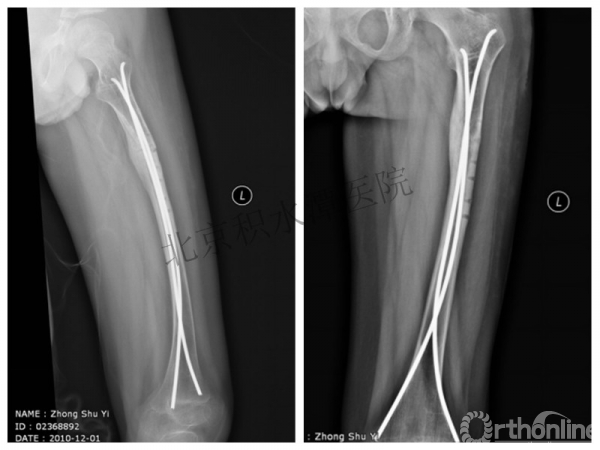

又过了4年!时间来到2015年

一年以后顺利愈合,实则危机四伏

数月后再骨折!牵引!

髋人字支具

外固定架术后一年